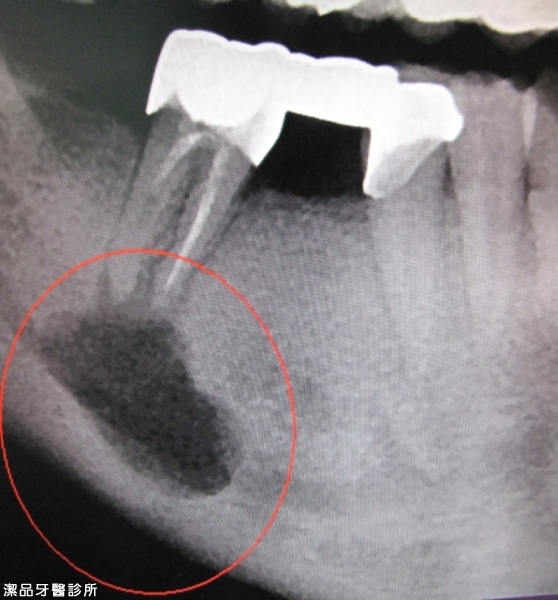

根管重新治療案例-001

案例簡述:

根管重新治療

治療後 (ㄧ年後) 重新根管治療+台大手術一年後可見齒槽骨修復中